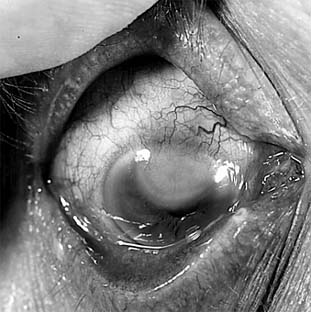

Unlike recurrent HSV keratitis that usually affects only the epithelium, VZV keratitis affects the stroma and anterior uvea at onset. The epithelial lesions are blotchy and amorphous except for an occasional linear pseudodendrite that only vaguely resembles the true dendrites of HSV keratitis. Stromal opacities consist of edema and mild cellular infiltration and initially are subepithelial. Deep stromal disease can follow with necrosis and vascularization (Figure 6-6). A disciform keratitis sometimes develops and resembles HSV disciform keratitis. Loss of corneal sensation is always a prominent feature and often persists for months after the corneal lesion appears to have healed. The associated uveitis tends to persist for weeks or months, but with time it eventually heals. Scleritis (sclerokeratitis) can be a serious feature of VZV ocular disease.

Figure 6-6

Figure 6-6: Herpes zoster keratitis.